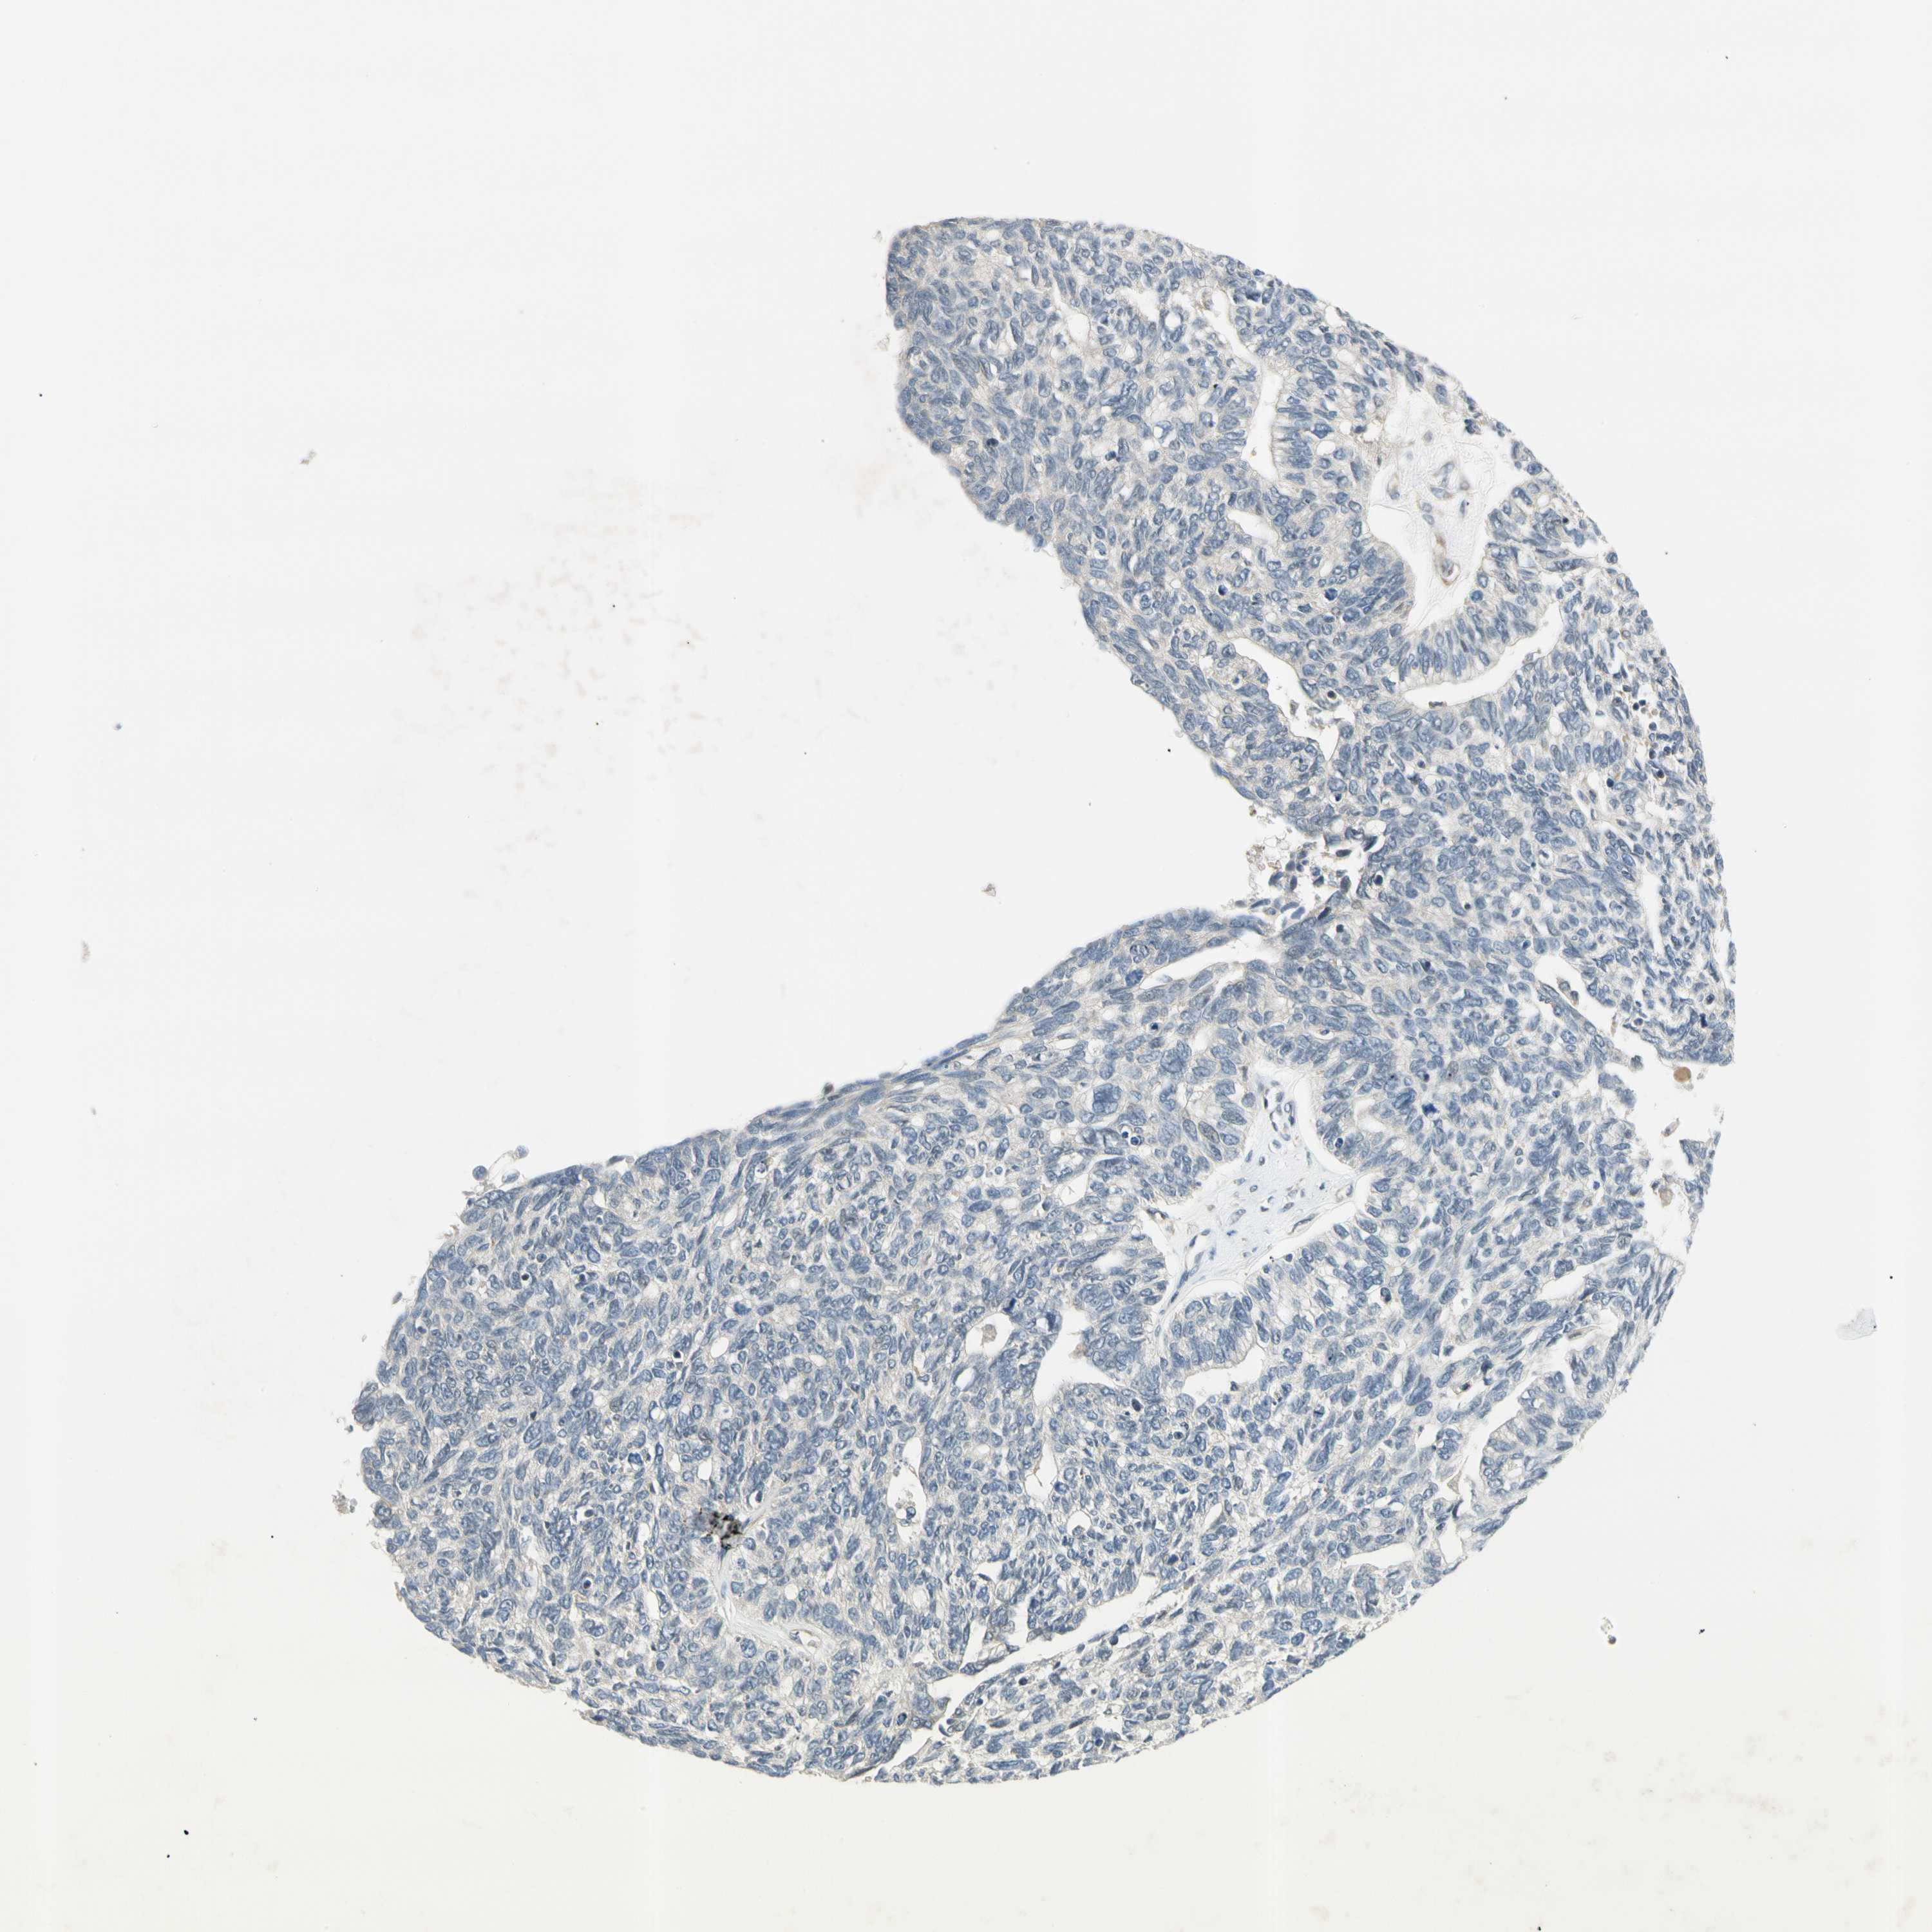

OVARIAN CANCER - Protein expressioni

A mouse-over function shows sample information and annotation data. Click on an image to view it in a full screen mode. Samples can be filtered based on level of antibody staining by selecting one or several of the following categories: high, medium, low and not detected. The assay and annotation is described here.

Note that samples used for immunohistochemistry by the Human Protein Atlas do not correspond to samples in the TCGA dataset.

Antibody stainingi

Antibody staining in the annotated cell types in the current human tissue is reported as not detected, low, medium, or high, based on conventional immunohistochemistry profiling in selected tissues. This score is based on the combination of the staining intensity and fraction of stained cells.

Each image is clickable and will lead to virtual microscopy that enables deeper exploration of all samples and also displays staining intensity scores, fraction scores and subcellular localization as well as patient and tissue information for each sample.

Antibody HPA008812

Staining

High

Medium

Low

Not detected

Intensity

Strong

Moderate

Weak

Negative

Quantity

>75%

75%-25%

<25%

None

Location

Nuclear

Cytoplasmic/membranous

Cytoplasmic/membranous,nuclear

Cystadenocarcinoma, serous, NOS

Carcinoma, endometroid

Cystadenocarcinoma, mucinous, NOS

Carcinoma, NOS